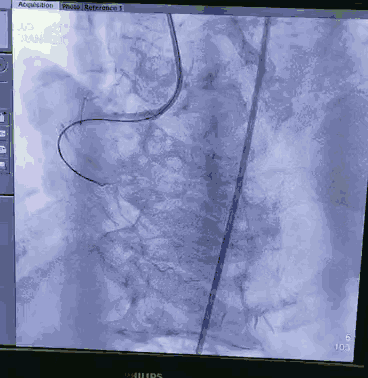

顺利跨瓣,测得跨瓣压差62mmHg。送20mm球囊扩张主动脉瓣,经右桡动脉猪尾导管造影,冠脉切线位未见右冠脉显影。为策安全,决定对RCA行冠脉保护,送JR4导管及guidzila和3.5球囊行冠脉保护。置入24mm微创 vitaflow瓣膜标准位释放。复查造影显示少量主动脉瓣返流,左右冠显示良好,撤除右冠保护。术后测压差为10mmHg。缝合双侧股动脉。术后恢复良好,次日转回普通病房,顺利出院。